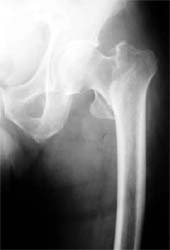

股骨颈骨折,采用闭合空心钉内固定。